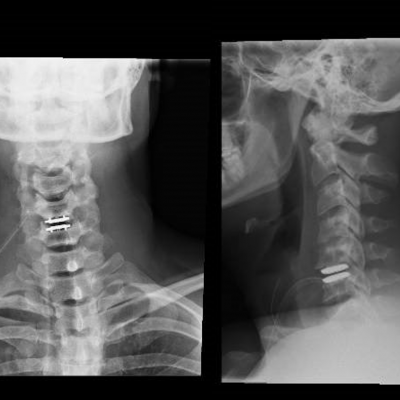

En la disertación el Dr. Zapata presentó el caso de un deportista profesional, jugador defensa central de un equipo de fútbol, que sufrió una hernia de disco cervical y fue tratada en el Hospital FM Habana con prótesis de disco.

La artroplastia de disco cervical puede ser una opción de tratamiento satisfactoria para deportistas con discopatía cervical, permitiendo una vuelta precoz y sin secuelas a la práctica deportiva, ya que es una técnica sin limitación de la movilidad.

Este tipo de cirugía permite la realización precoz de ejercicios y actividades, y no precisa de collarín postoperatorio.

En las conclusiones del caso, compartió los resultados con una recuperación completa en unas semanas, así como la rápida incorporación al equipo, manteniéndose activo y titular como defensa central. Tres años después continúa al mismo nivel sin complicaciones, confirmando el éxito del tratamiento.